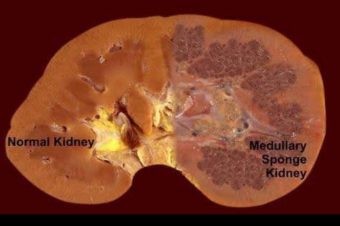

کلیه اسفنجی (MSK)، یک اختلال مادرزادی است، به این معنی که در هنگام تولد وجود دارد. کلیه اسفنجی زمانی رخ می دهد که کیست های کوچکی در روی لوله های کوچک داخل کلیه (به نام توبول) یا روی مجاری جمع کننده (کانالی که ادرار را برای خروج جمع آوری می کند) تشکیل می شود. این کیست ها می توانند جریان خروجی از کلیه ها را کاهش دهند. یکی از کلیه ها یا هر دوی آن ها می توانند درگیر شوند.

Medullary sponge kidney is a congenital disorder meaning you’re born with it. This condition causes small, fluid-filled cysts to form in the medulla of your kidneys.

کلیه اسفنجی مدولاری یک اختلال مادرزادی است، به این معنی که شما با آن متولد میشوید. این وضعیت باعث میشود کیستهای کوچک و پر از مایع در مدولای کلیههای شما تشکیل شوند.